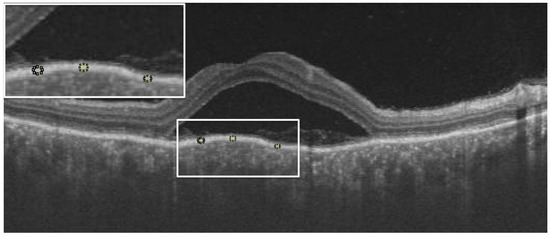

From the OCT images, the central macular thickness (CMT), retinal pigment epithelial (RPE), total choroidal thickness (CT), as well as RPE reflectivity, were analyzed. The analysis was done using ImageJ software by Fiji. During the acute phase of the disease, RPE reflectivity was calculated within the area of RPE below the fovea, below the detached retina, and below the areas of the attached retina (Figure 1). The oval selection tool of ImageJ was used to manually mark an elliptical region of interest within the RPE to measure the reflectivity in that area, i.e., the mean grey value [12]. RPE thickness was also calculated in the subfoveal area, below the area of the attached retina and the area of the detached retina, using the in-built calliper tool in ImageJ (Figure 2). Three adjacent locations were taken in all the areas measured, i.e., under the fovea and in the areas of attached and detached retina, for both RPE reflectivity and thickness measurements, which were then averaged. Total choroidal thickness was measured in the subfoveal area. The total choroidal thickness was measured from the outer border of the RPE to the inner border of the sclera. Measurements post-resolution of the disease were done in locations identical to the pretreatment measurements on the OCT B-scan, enabled by image registration. Morphological features that were analyzed included subretinal hyperreflective dots, choroidal hyperreflective dots, bacillary layer detachment, and RPE vacuolations.

Figure 1. Example showing measurement of retinal pigment epithelial (RPE) reflectivity (white dotted circles in the white box inset at top left corner) below detached retina using ImageJ software. An average of the values from these three areas were taken for RPE reflectivity in detached retina. Similar measurements were taken under attached retina and subfoveally in all eyes.